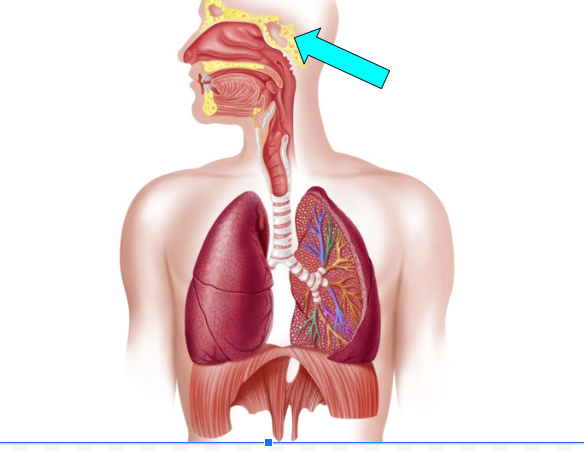

Sphenoidal Sinus(pic)

Sphenoidal Sinus

helps to humidify & warm air, trap & flushes out germs